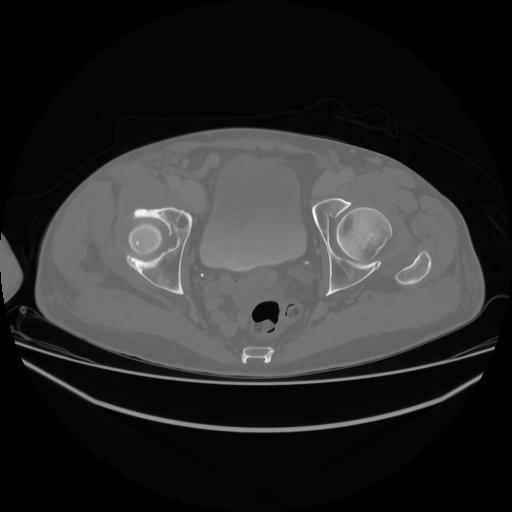

5 CUERPO,CE,Vol,1.0,CUERPO,,